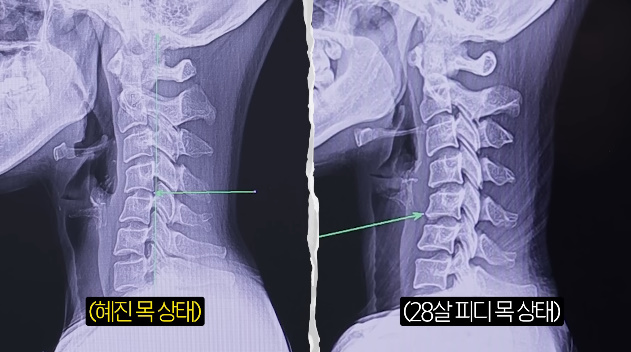

그 뒤 엑스레이 촬영을 했고, 결과물을 본 의사는 "통증이 계속 재발할수밖에 없는게 목이 역커브다"라고 심각한 상태를 지적했다. 한혜진은 "얼굴쪽으로 C자 커브가 있어야하는데 일자다 못해 뒤로 약간 가고있는것 같다"라고 놀랐고, 의사도 "역 C자다"라고 짚었다.

그는 "다행인건 신경공 자체는 좁아지지 않아서 아직 손 저림이 심하거나 그럴것같진 않다. 목디스크로 진행되면 손 저림도 심해지는거다. 신경이 눌리면 저리고 그런다. 어느정도 눌리냐에 따라 신경차단술주사 치료를 하거나 수술하는 경우도 있다. 지금 거북목이 너무 심하고 목이 좀 길기때문에 거북목이 잘 오는 스타일이다. 목이 길면 좀 더 약할 확률이 크다"고 말했다.

한혜진은 "다시 정상적인 C자 커브로 만들수 있냐"고 물었고, 의사는 "아직은 퇴행성 변화가 심하지 않기때문에 어느정도 커브는 만들수 있다. 생활습관 교정하면 어느정도까지는 가능하다"며 "또 어깨 사진에서 보면 어깨 충돌증후군이 있다. 어깨도 회전근개 강화 운동하고 옆으로 자거나 플랭크, 푸시업 이런건 안하는게 좋다"고 당부했다.

이에 한혜진은 "여기 환자분이 100분이 내원하면 저는 몇등정도냐"고 궁금해 했고, 의사는 "상위 10등안에 든다고 봐야한다. 안 좋은걸로"라고 말해 한혜진을 충격케 했다. 그러자 그는 "저희 피디님도 사진을 찍었다"고 말했다. 앞서 한혜진과의 비교를 위해 어린 피디도 함께 엑스레이 촬영을 진행했던 것.

하지만 의사는 "더 안좋다"고 반전 결과를 전했다. 한혜진은 다급히 PD를 불렀고, "피디님 큰일났다. 빨리 앉아라"고 말했다. 의사는 "환자분은 목이 안 아프냐"고 물었고, PD는 "아프다고 느껴본적 없다"고 털어놨다. 의사는 "핸드폰 많이 보지말라"고 지적했다. 이어 "요즘 오래 핸드폰보고 하니까 고등학생도 목디스크가 오는 경우가 있다. 물리치료나 운동치료, 집에서 할 수 있는 운동좀 배워가서 해보고 경과를 보자"고 전했다.